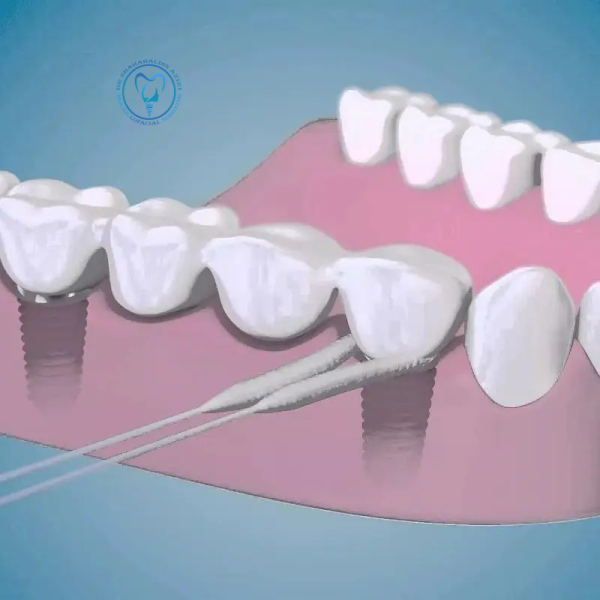

استفاده از نخ دندان برای دندان ایمپلنت شده

اهمیت استفاده از نخ دندان برای دندانهای ایمپلنتشده ایمپلنتهای دندانی جایگزینهای مصنوعی برای دندانهای از دسترفته هستند که به استخوان فک متصل میشوند و عملکردی مشابه دندانهای طبیعی دارند. حفظ بهداشت دهان و دندان برای موفقیت و دوام ایمپلنتها بسیار حیاتی است. یکی از روشهای کلیدی در این زمینه، استفاده صحیح از نخ دندان است.…